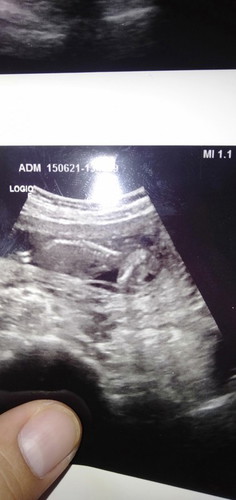

16สัปดาห์2วัน หมออัลตราซาวด์ว่าไม่เห็กระโหลกศีรษะ

พรุ่งนี้หมอนัดไปโรงบาลใหญ่ให้หมอด้านเชี่ยวชาญซาวด์อีกรอบ...หัวใจเต้นปกติขาแขนเห็นหมด..แม่เศร้าใจมากค่ะ😞 กลัวมากตอนนี้เครียดมากค่ะ

เพิ่งไปซาวด์มาเหมือนกันค่ะ หมอคุยกันเหมือนมีปัญหาอะไรบางอย่างใช้ภาษาหมอเราฟังไม่ออก จับใจความว่า ไม่มีหรืออาจจะยังไม่เห็นถ้ากังวลก็นัดเค้ามาอีกรอบ สรุป นัดมาอีกรอบจริงๆค่ะโดยไม่แจ้งอะไรเราเลยว่าทำไมถึงนัดซาวด์อีก ไม่กล้าถามด้วยค่ะ กลัวคำตอบ🥺